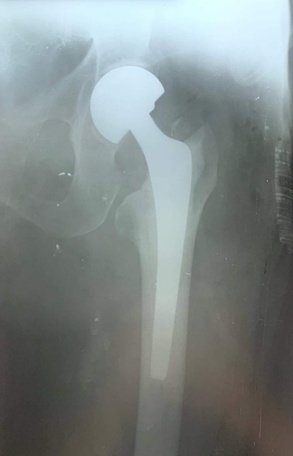

При огляді: положенння хворої пасивне на каталці, хвора вказує на біль в області лівого кульшового суглобу що посилюється при пальпації та спробі рухів у суглобі. Ліва н\кінцвка ротована до зовні. Позитивний симптом «прилиплої п’яти». Вкорочення лівої н\к до 3х см. Проведено рентгенографію лівої стегнової кістки з кульшовим суглобом. Встановлено діагноз: Закритий трансцервікальний (Клас АО 31.В2) зі зміщенням.

Хвора госпіталізована в травматологічне відділення для подальшого дообстеження та оперативного лікування з тимчасової фіксацією лівої нижньої кінцівки для зменшення больового синдому. В умовах травматологічного відділення хвора була дообстежена та оглянута суміжними спеціалістами терапевтом, кардіологом, анестезіологом.

Протягом 28 годин від отримання травми хвора була прооперована. Геміартропластика лівого кульшового суглобу. Після оперативного втручання хвора перебувала під наглядом у відділенні інтенсивної терапії. На 2гу добу хвора переведена в травматологічне відділення. В травматологічному відділення хворій під наглядом лікуючого лікаря було дозволено сідати у ліжку. На 3 тю добу хвора під наглядом лікуючого лікаря з допомогою вставала та пересувалася біля ліжка в палаті. На 5 ту дому після оперативного втручання хвора самостійно пересувалася в межах травматологічного відділення. На 12 добу хворій було знято шви з рани. Хвора в задовільному стані виписана, і самостійно залишила лікувальний заклад. Надано рекомендації з приводу подальшого лікування в амбулаторних умовах.